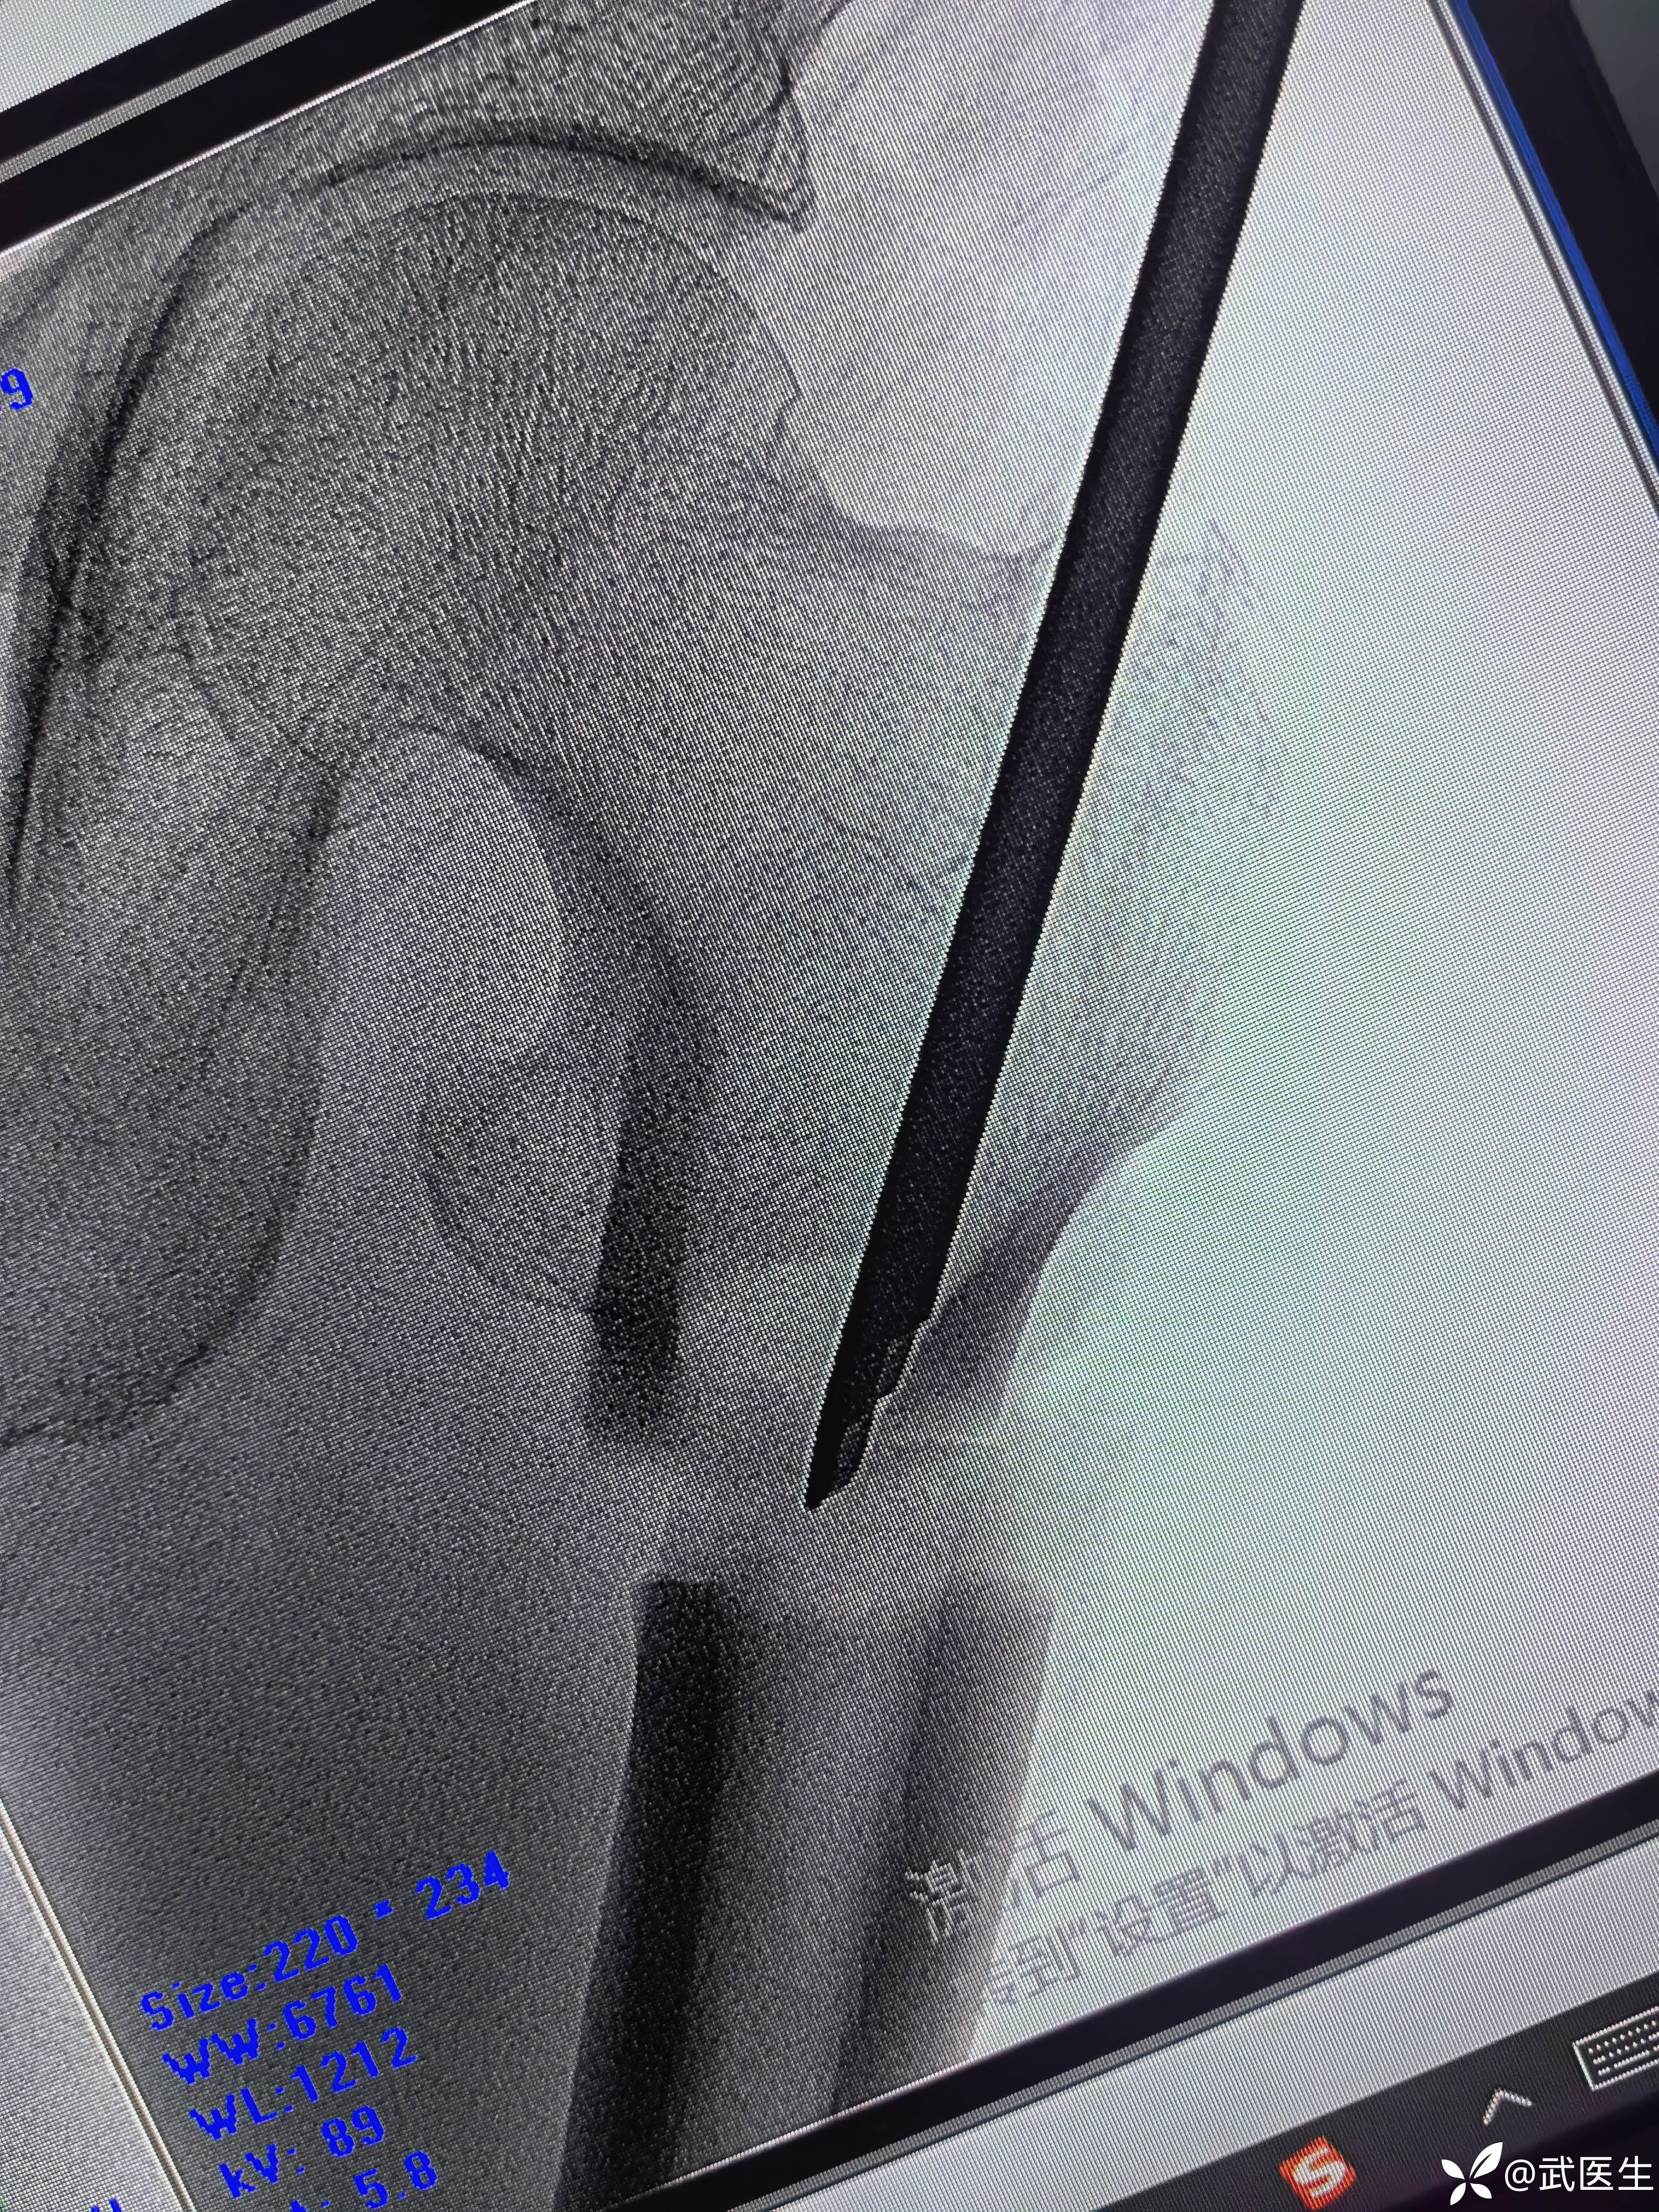

分享一例髓内钉治疗股骨近端骨折病例

男,66岁,摔伤致左大腿疼痛活动受限三小时就诊,门诊以“左股骨干骨折”为诊断收住入院,上图

股骨近端骨折,老先生挺瘦,很奇怪的是,大腿几乎无肿胀,入院后骨牵引,老先生也没怎么感觉骨折部位特别疼痛。

常规侧卧位,定位

合适入针点,开口,对位差,手法复位